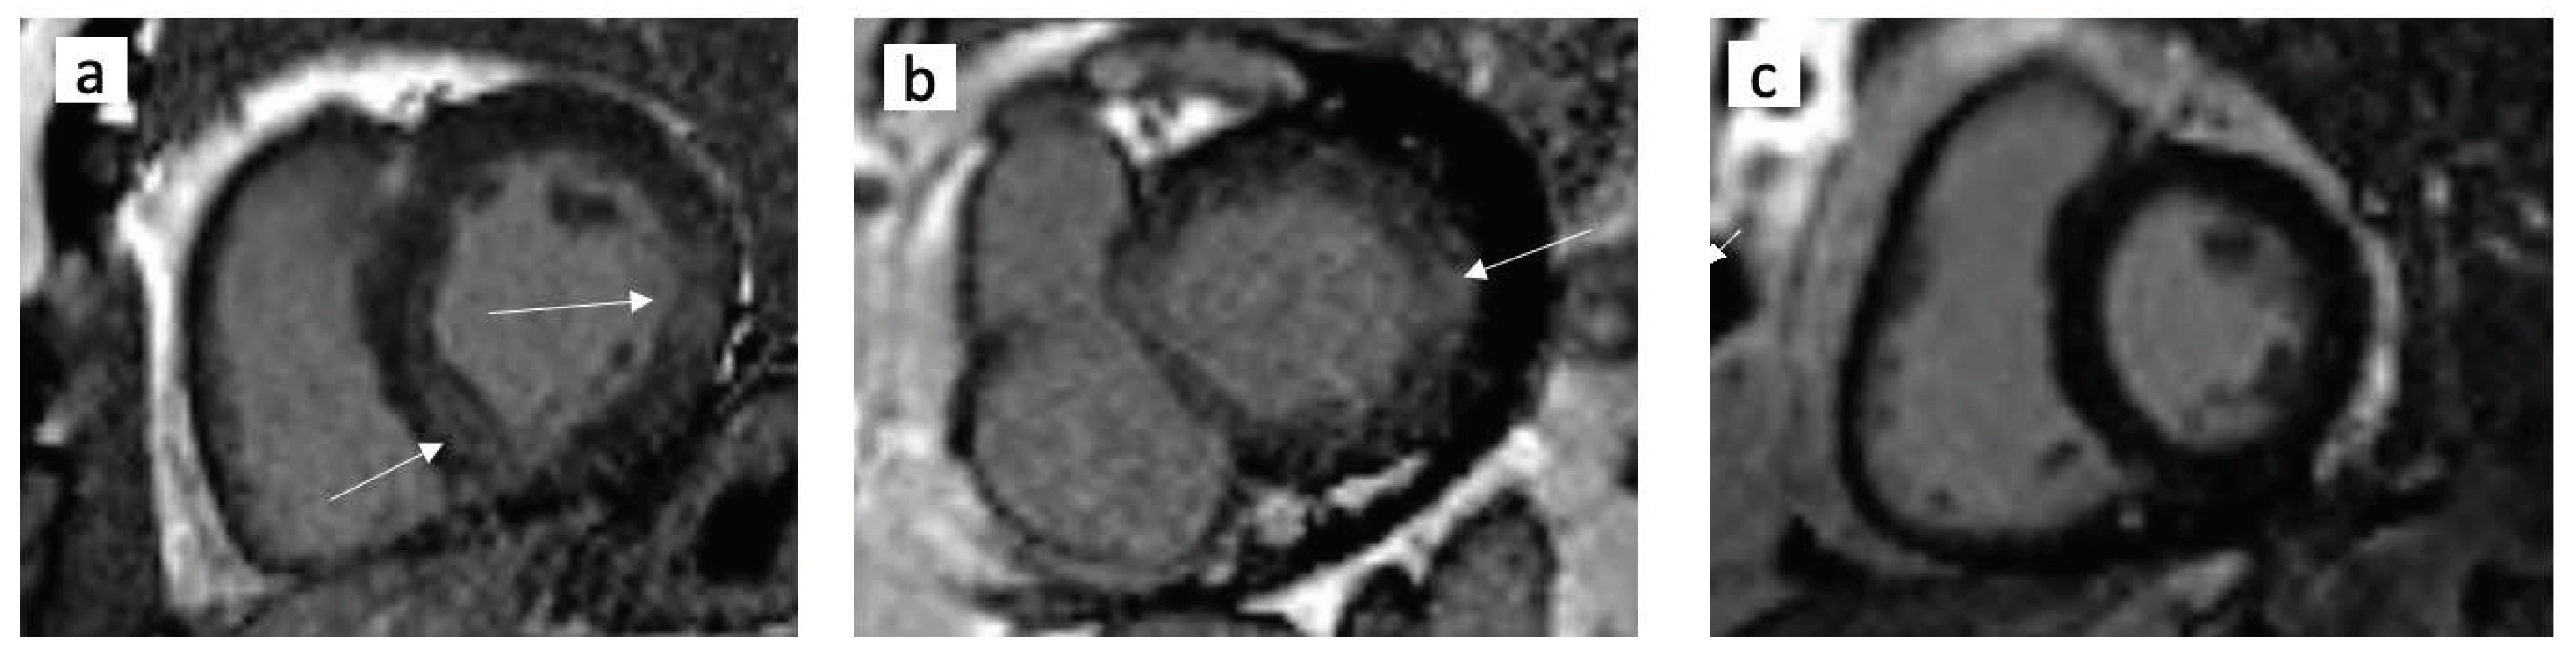

2.7. Cardiac MRI